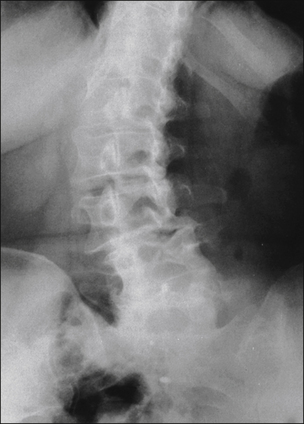

The majority of patients with complaints of low back pain (with or without leg pain) has associated spondylotic spinal disease (Fig. 71-2, Box 71-3). These spondylotic changes may be defined as primary loss of hydration of the lumbar discs with a subsequent change in signal characteristics and associated ligament thickening, chronic inflammatory changes in ligaments and adjacent end plates, loss of disc height, facet arthropathy and hypertrophy (with or without associated canal and foraminal stenosis), or evidence of instability. The presence of spondylosis and the complaints are at least correlated, but the correlation is far from certain (Boden et al 1990, Weber 1994). The diagnostic problem is that a substantial number of patients have spondylotic changes without any apparent related symptoms (Wiesel et al 1984, Boden et al 1990).

Figure 71-2 Anteroposterior plain radiograph of the lumbar spine demonstrating dramatic kyphoscoliosis involving lumbar vertebrae 1–4 and the lower thoracic spine.

These structural deformities are often associated with severe pain and respond well to surgical correction.